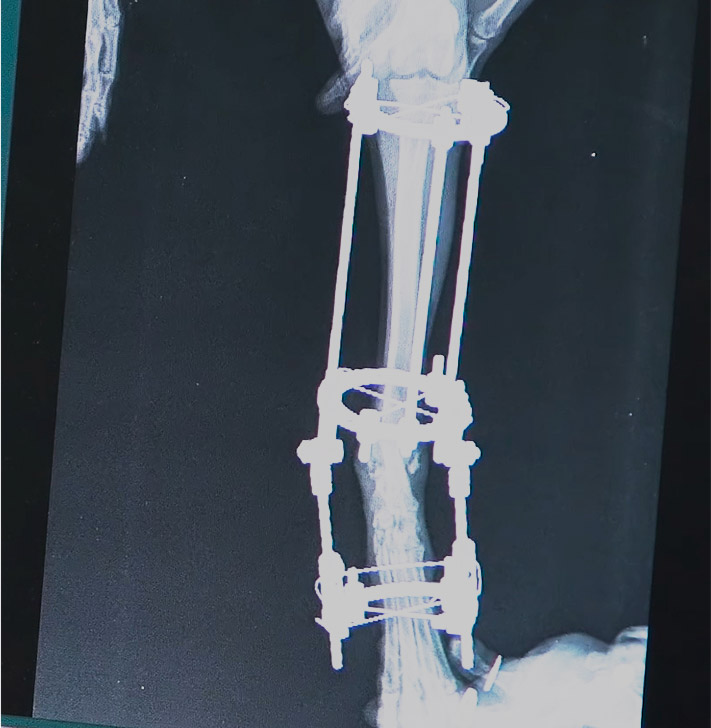

CURSO PRÁCTICO DE

TRATAMIENTO QUIRÚRGICO

DE DEFORMIDADES ANGULARES